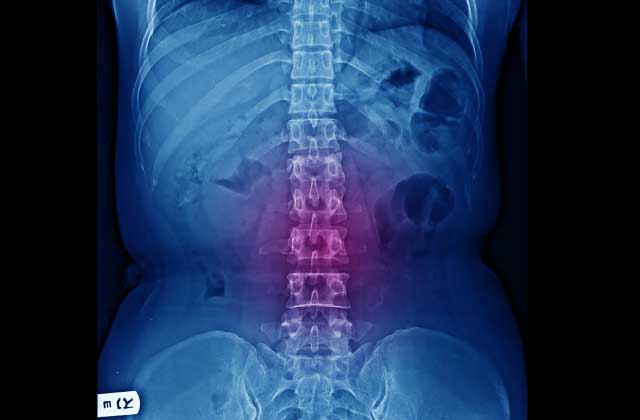

実は脊柱管狭窄症で悩んでいるほとんどの人が、背骨に歪みがあります。

背骨がゆがんでうまく動かないと、腰の仕事量が何倍にもなり背中の筋肉が硬くなったり、骨と骨の間が狭くなったりします。